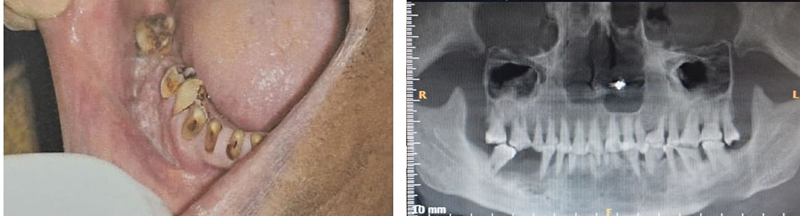

| Fig 1 : Clinical and radiographic image of a 54-year-old female patient with cancer of the lower right alveolus with no known risk factors apart from periodontitis.